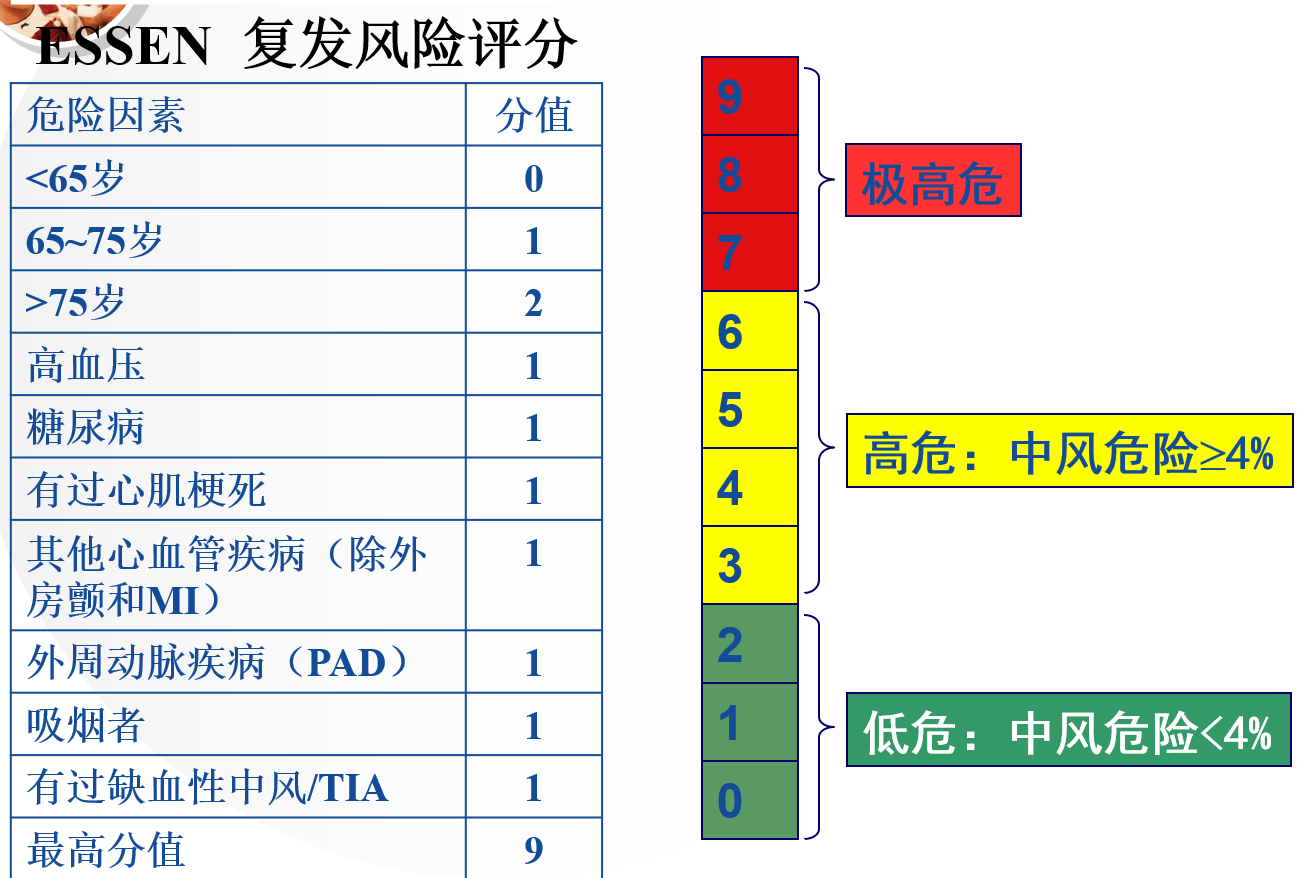

4.复发风险是怎么评估的呢?ESSEN评分

如果您患过中风或TIA,复发中风的风险就很大,那么要怎么评估到底有多大的风险,是否需要特别的治疗呢?

ESSEN 评分就是用来评估中风复发风险的专业方法,大家可以根据这个表上的方法试试看。这个表的最高分为9分,从0分到9分,得分越高发生中风的风险越大,

如果评分达到3分,就是中风复发高危患者,这时应该采取积极的二级预防预防治疗策略:除有效控制好血压、血脂和血糖水平外,抗血小板治疗是至关重要的,应该用抗血小板作用更强的药物(如波立维)治疗。